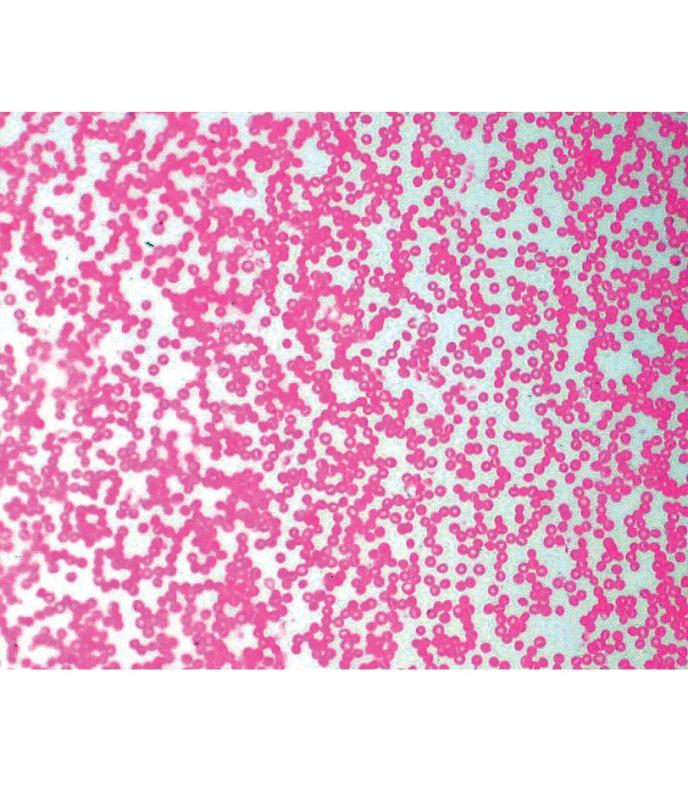

Athérosclérose, homme Préparation microscopique - Biologie animale - Pathologie À l'unité